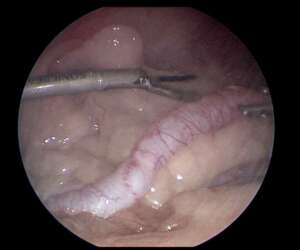

腹腔鏡でも子宮蓄膿症の手術ができることもあります(手術写真あり) 2025年09月24日 子宮蓄膿症と診断した場合の手術の方法として 子宮がパンパン過ぎなければ腹腔鏡で手術を行うことができます こんな感じで卵巣子宮全摘出をしていきます あまりに子宮が大きいと鉗子でもてないため通常の大きく切開する方法となります もし腹腔鏡でできた場合は このぐらいの傷ですみます 大きく切開するよりは負担が少なくなると思います 必ずできるものではありませんがもしお悩みの場合は一度相談してみてください